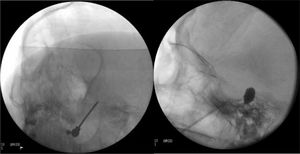

En todos ellos, el abordaje es similar y se realiza bajo radioscopia intraoperatoria, sedación y monitorización de constantes ante el riesgo de hipertensión arterial. El objetivo es canalizar con una aguja el foramen oval para introducir un electrodo en la termocoagulación (TMC), una sonda para inflar un balón (técnica de Mullan) o una cánula para inyectar sustancias (gangliólisis)25,70,71.

Termocoagulación del ganglio de Gasser. La aguja introducida en el foramen oval porta un electrodo para aplicar una radiofrecuencia térmica en el ganglio de Gasser (fig. 4a). Antes de ejecutar la radiofrecuencia se despierta al paciente, ya que tiene que colaborar en un test sensitivo en el que se realiza electroestimulación provocando parestesias para localizar la rama que se desea tratar. También se puede realizar bajo sedación, realizando una monitorización neurofisiológica intraoperatoria (estimulación antidrómica) que permite localizar las tres ramas del trigémino. En general, no se recomienda en NT de rama V1 por la posibilidad de que provoque un déficit sensitivo que afecte a la córnea.

Figura 4.A)Electrodo de radiofrecuencia térmica (termocoagulación) introducido a través del foramen oval en la proyección de Waters en una paciente con neuralgia del trigémino de rama V3 refractaria. B)Cánula provista de sonda de Fogarty n.°4 introducida a través del foramen oval e inflado del balón en una paciente de 84 años con neuralgia del trigémino de rama V2 refractaria (Hospital de la Santa Creu i Sant Pau).

Compresión percutánea con balón del ganglio de Gasser. Conocida como técnica de Mullan, consiste en la introducción a través del foramen oval de una aguja de 15G provista de una sonda con un balón de Fogarty número4, bajo radioscopia y anestesia general, pues no precisa la colaboración del paciente. A continuación se procede al hinchado del balón con contraste hasta 0,7-0,75cc de volumen y 650-950mmHg de presión, visualizando en radioscopia el balón en forma de pera invertida o de reloj de arena en el cavum de Meckel (fig. 4b). La compresión se mantiene 60-120segundos y después se deshincha. El hinchado del balón puede comportar bradicardia y crisis/emergencia hipertensiva.